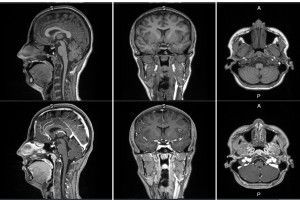

- GE HealthCare Announces First Patient Dosed in Phase 2/3 LUMINA Trial for Manganese-Based MRI Contrast Agent Under FDA Fast Track Designation, Further Advancing Its Innovation Pipeline of Novel Imaging Agents

- GE HealthCare (Nasdaq: GEHC) today announced the first patient has been dosed in the international, multi-center Phase 2/3 LUMINA clinical trial of its manganese-based magnetic resonance imaging (MRI) contrast agent, mangaciclanol, at Mayo Clinic ...